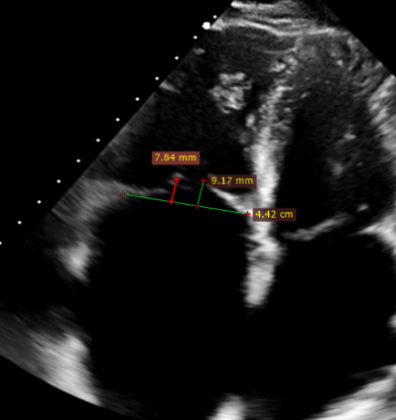

- Massive tricuspid regurgitation (5+, mean vena contracta 14mm);

- Regurgitant orifices located at antero-septal, central, and postero-septal regions, with a significant gap at the antero-septal region (antero-septal gap 9.1mm), leaflet tethering (tethering height approximately 9mm);

- Tricuspid annular dilation (mean annulus diameter: 43mm);